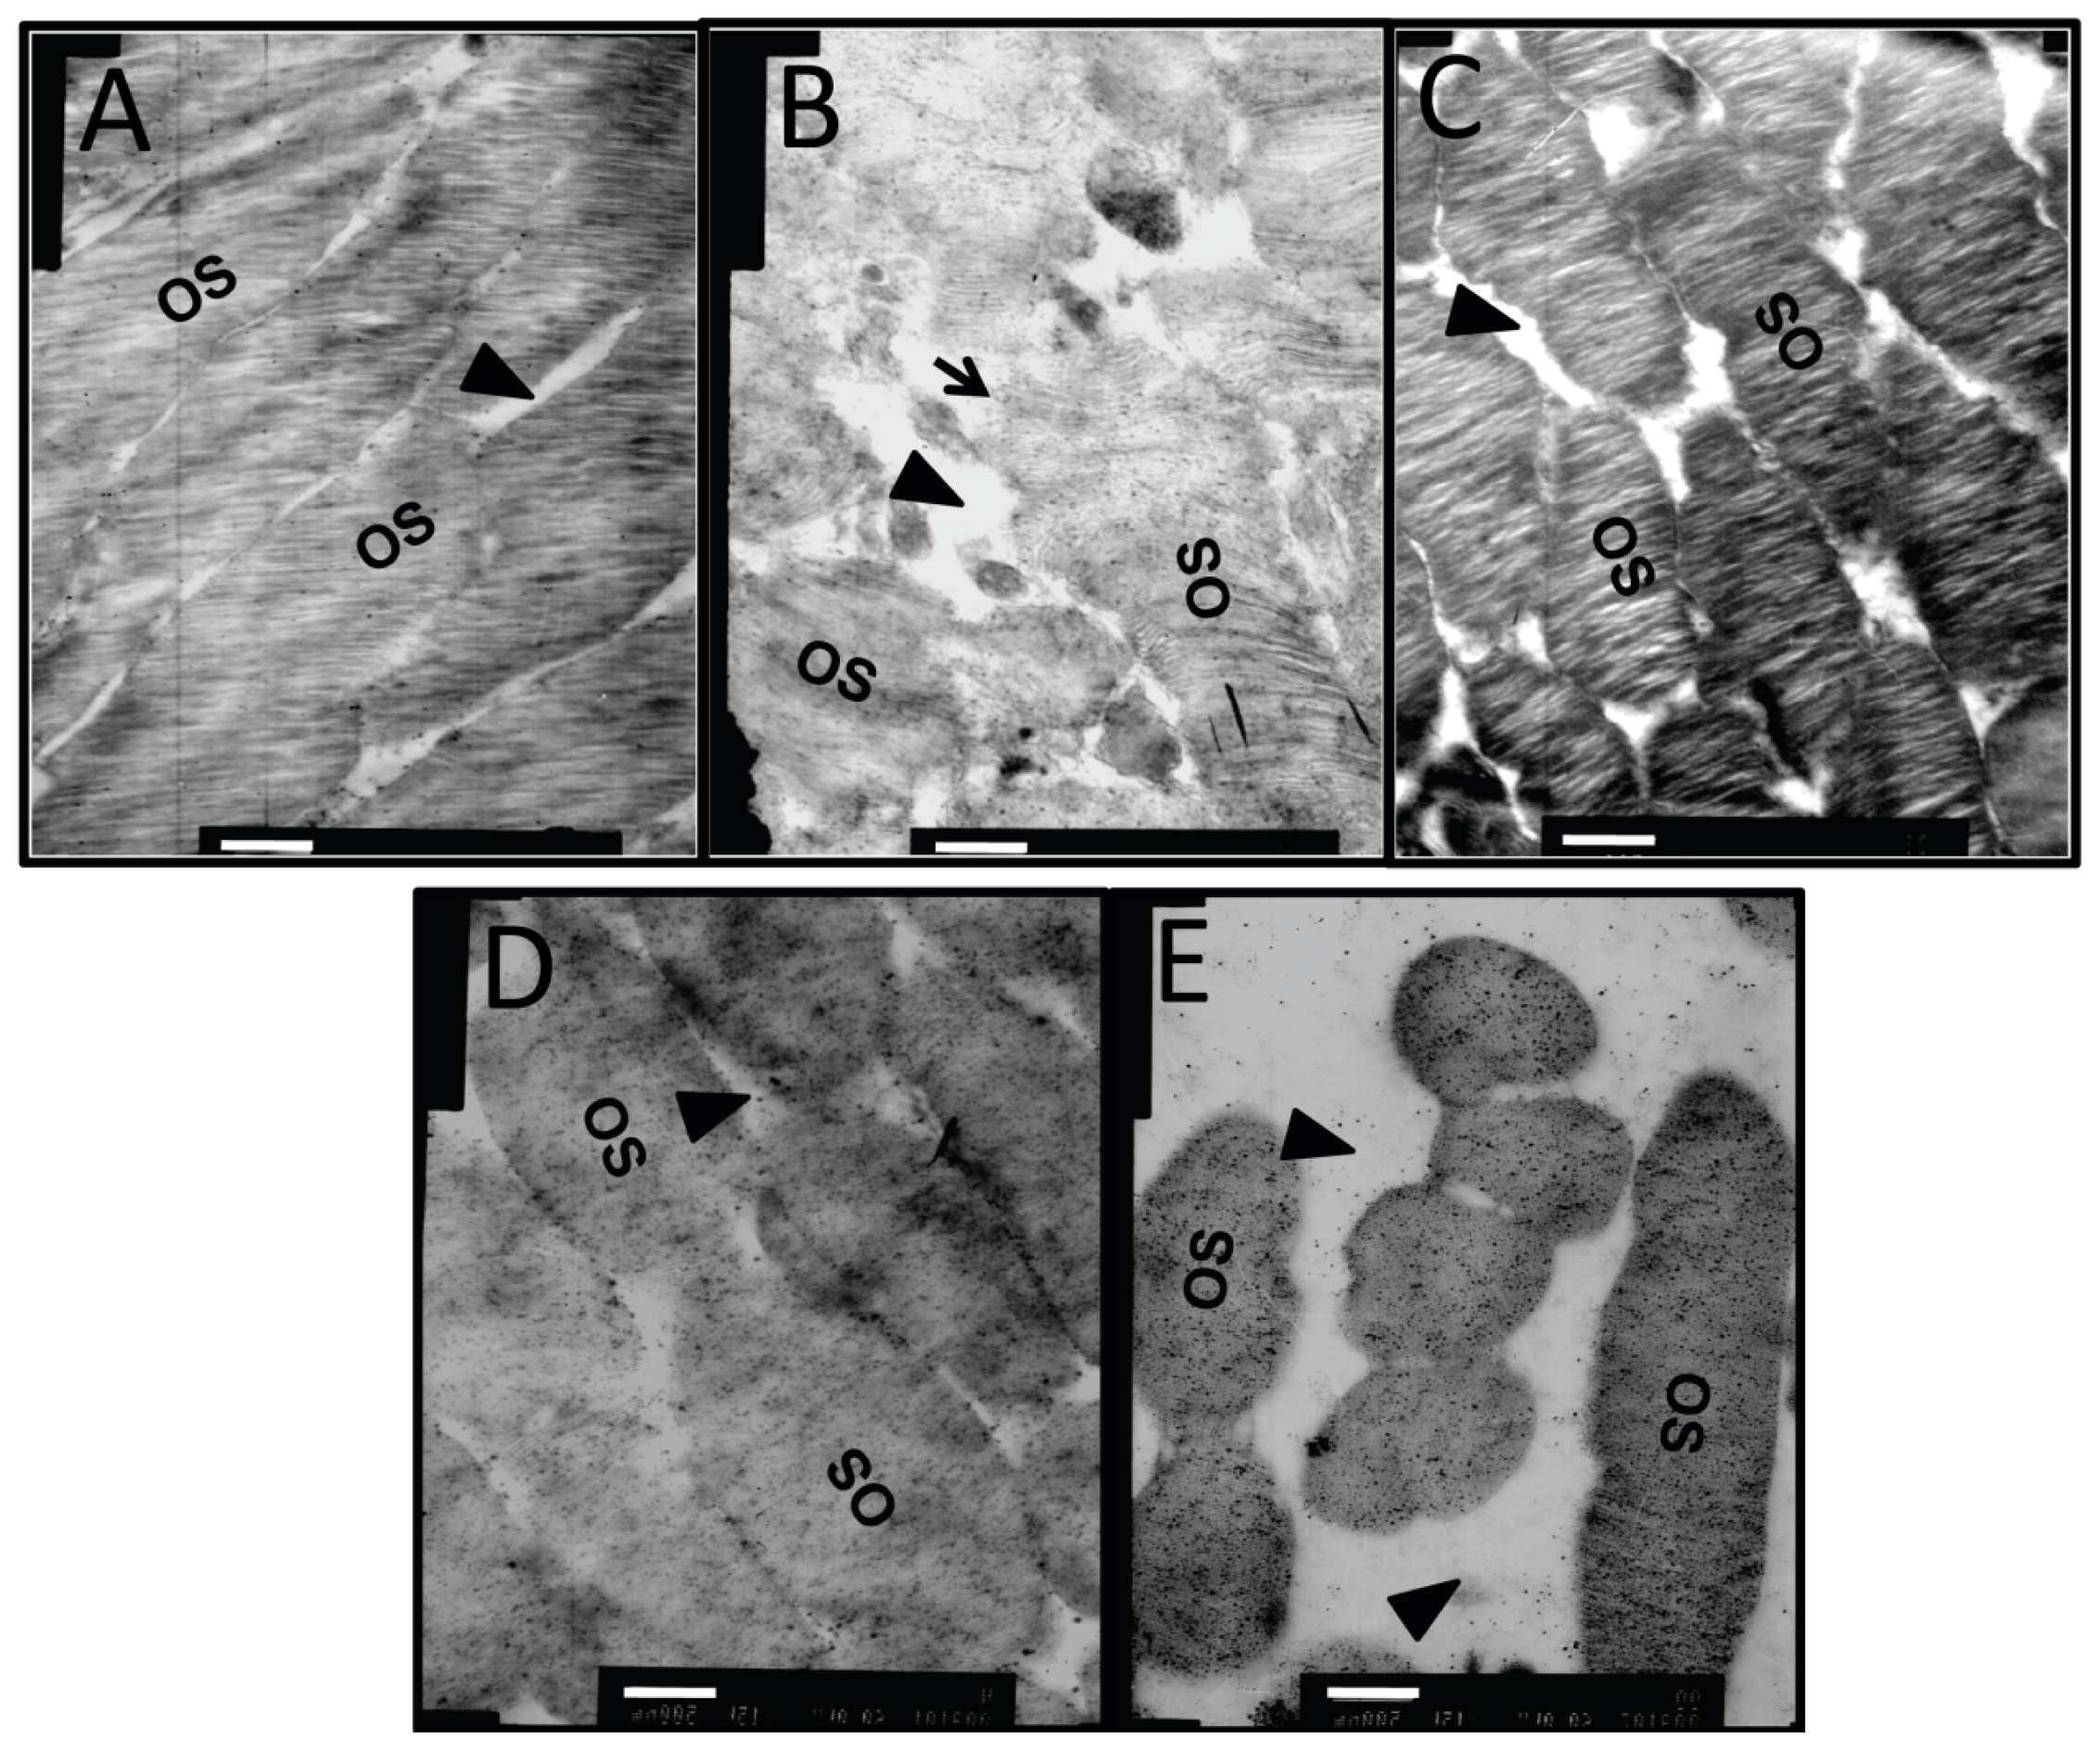

In the retina of normal controls (Figure 7A), the capillary lumen (black triangle) was smooth and intact, with red blood cells passing through. The thin sheath of endothelial cells (black arrow) closely attached to the continuous base membrane. The photoreceptor outer segments (OS) were intact and organized with little space (black triangle) between them (Figure 8A). In diabetic retinas without intervention, heterochromatin margination (white arrow), kidney-shaped swelled nucleus, and multiple secondary lysosomes were observed in microvessel endothelial cells (black arrow), and retinal capillary lumen was narrowed and ill-defined (Figure 7B). The organization of OS was disrupted, the gap between OS became larger (black triangle), and some structures of the OS were blurred due to breakage and dissolution of membrane discs (black arrow) (Figure 8B). Notably, the capillary lumen (black triangle) in retina of the dual-target intervention group (Figure 7C) was unobstructed, in which passing red blood cells were seen. Endothelial cells (black arrow) in this group were slightly swelled, and pericytes were clear and intact (Figure 7C). Moreover, photoreceptor OS in this group was organized with a discernible structure of the membrane discs, and the inter-OS space was much reduced compared to that in diabetic retina without intervention (black triangle) (Figure 8C). In contrast, stenotic retinal capillary lumen (black triangle) and deformed red blood cells were observed in both single-target intervention groups (Figure 7D,E). Swelled endothelial cells (Figure 7D,E, black arrow), marginalized heterochromatin (Figure 7D,E, white arrow), and loosely organized photoreceptor OS with a blurred membrane disc structure (Figure 8D,E) were also found in the retina of these groups. The TEM results indicate that the ultrastructure of retinal microvessels and photoreceptor OS in the dual-target intervention group were less damaged than the single-target and non-intervention groups, suggesting the greater effectiveness of the dual-target intervention on diabetic retina.

Figure 8.

The ultrastructural changes in the retinal photoreceptor outer segment of diabetic rats after dual-target intervention. Representative TEM images of retinal photoreceptor outer segments in normal controls (A); diabetic rats without intervention (B); diabetic rats with dual intervention (C); and diabetic animals with ranibizumab (D) or CTGF shRNA single intervention (E) are shown (n = 5). Black triangles designate the gap between outer segments, black arrow shows the dissolved membrane discs. OS: outer segment. Scale bar = 500 nm.